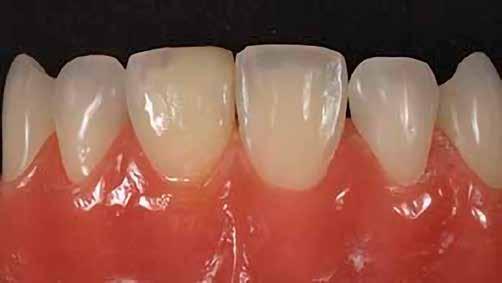

12. ábra: A premoláris fogak preoperatív állapota.

13. ábra: A premoláris fogak postoperatív fotója.